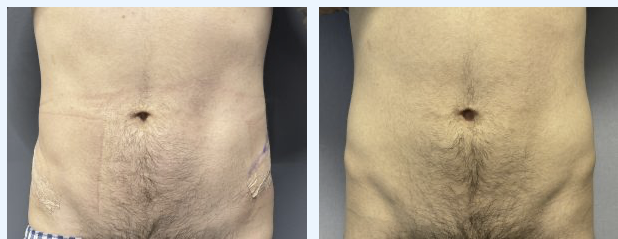

ive been cursed with shitty hips that make it look like im a fatass even while low bf%

Risks include: